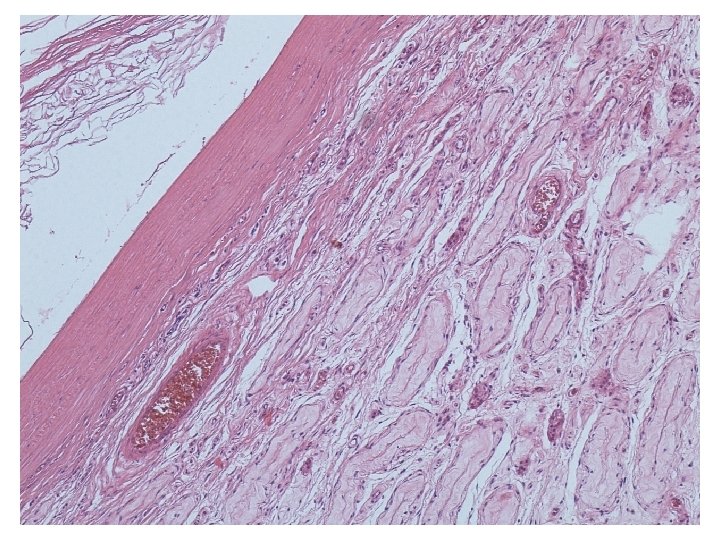

Mikroskopické vyšetření • tkáň varlete se stěnou cysty tvořenou různě silným hyalinizovaným vazivem s různě intenzivní kulatobuněčnou zánětlivou celulizací, která je ložiskově vystlaná zachovalým rohovějícím vrstevnatým dlaždicovým epitelem • v lumen cystického útvaru keratinové hmoty • v okolí cystického útvaru atrofické a hyalinizované semenotvorné kanálky

teratom prepubertálního typu (nezávislý na intratubulární germinální neoplázii), tzv. epidermální cysta